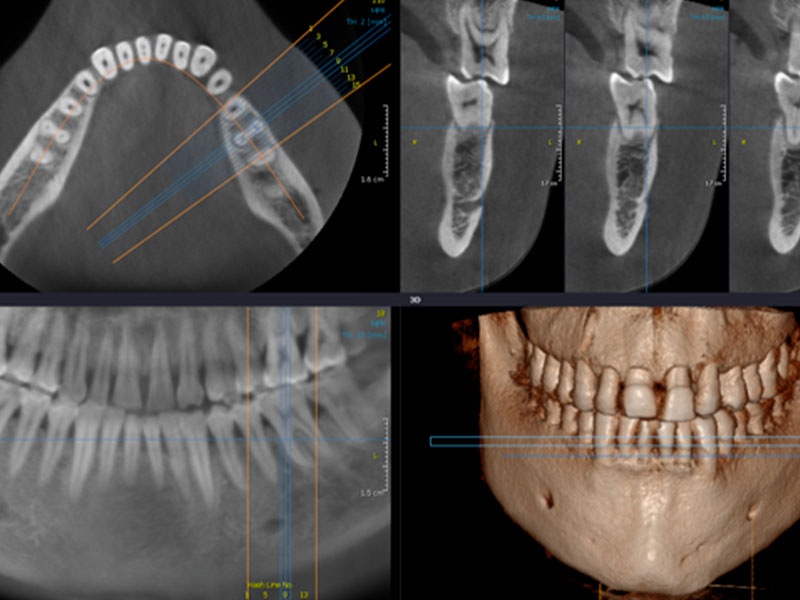

La TC Cone Beam è una tecnologia all’avanguardia che consente di ottenere immagini tridimensionali di altissima qualità sottoponendo il paziente a dosi molto basse di radiazioni. Si ottengono immagini tridimensionali e ricostruzioni multiplanari (MPR) su vari piani di osservazione. Le immagini sono caratterizzate da elevata risoluzione spaziale e dalla corrispondenza alla realtà anatomica (rapporto 1:1).